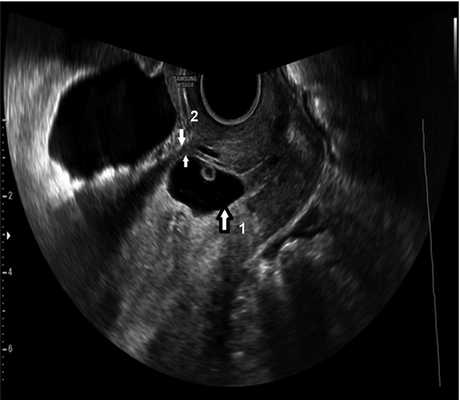

У 14 (73,7%) пациенток при типичной локализации плодного яйца в проекции рубца после кесарева сечения выявлено истончение миометрия передней стенки с остаточной толщиной миометрия менее 2 мм, деформацией передней стенки матки, «выбуханием» плодного яйца в сторону мочевого пузыря (рис. 2). В двух наблюдениях имелись признаки инвазии хориона в миометрий (рис. 3). С учетом высокого риска гестационных осложнений в виде врастания плаценты, кровотечения, разрыва матки беременным было предложено прерывание беременности с одновременной метропластикой.

Рис. 2 Беременность в рубце с признаками его несостоятельности, истончение миометрия.

1 — плодное яйцо; стрелками указан остаточный миометрий.